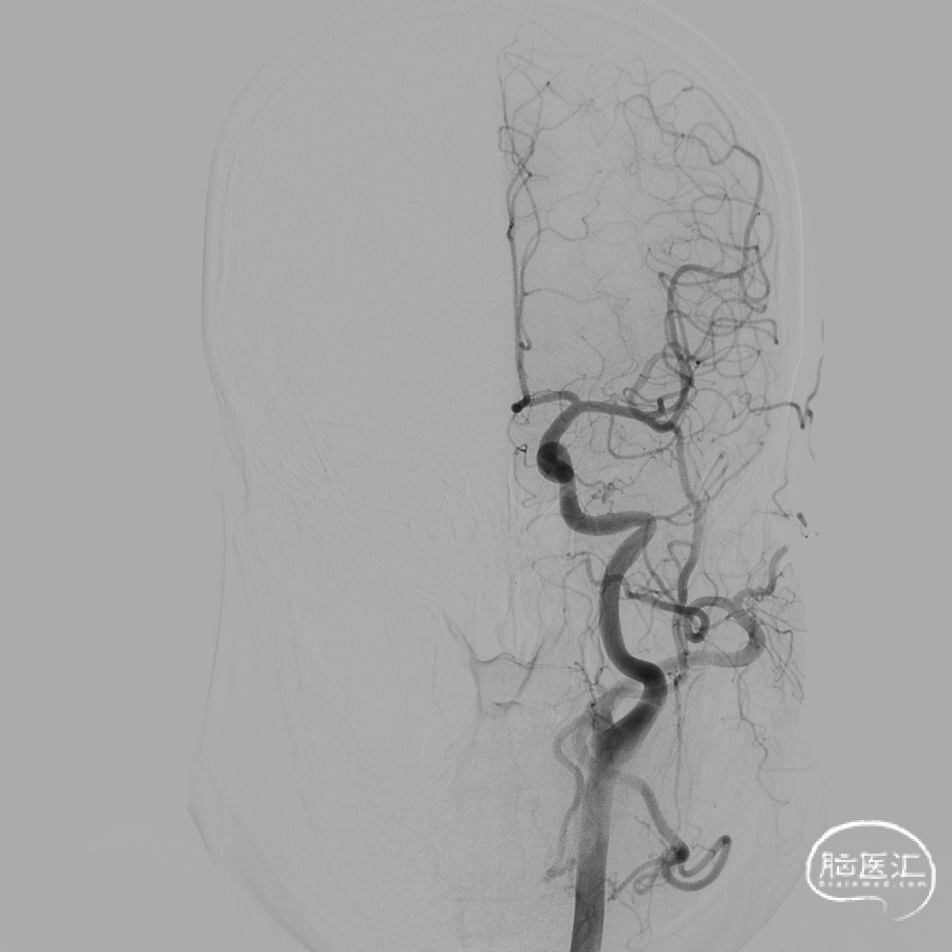

DSA:DSA提示右侧大脑中动脉M1段动脉瘤,左侧大脑前动脉A1段发育不良。

其他血管造影未见明显异常。

术前诊断:动脉瘤位于M1主干,考虑夹层动脉瘤可能大。

载瘤动脉远端血管直径:2.4mm

载瘤动脉近端血管直径:2.5mm

动脉瘤尺寸:(瘤颈口宽度2.0mm/瘤体高度1.86mm/瘤囊宽度1.85mm)

密网支架:强易达Choydar血流导向装置 FD250-15

术后造影:支架充分覆盖动脉瘤瘤颈,贴壁良好,瘤体内可见造影剂滞留。

术后支架显影:定位精准,未覆盖颞前动脉及大脑前动脉。